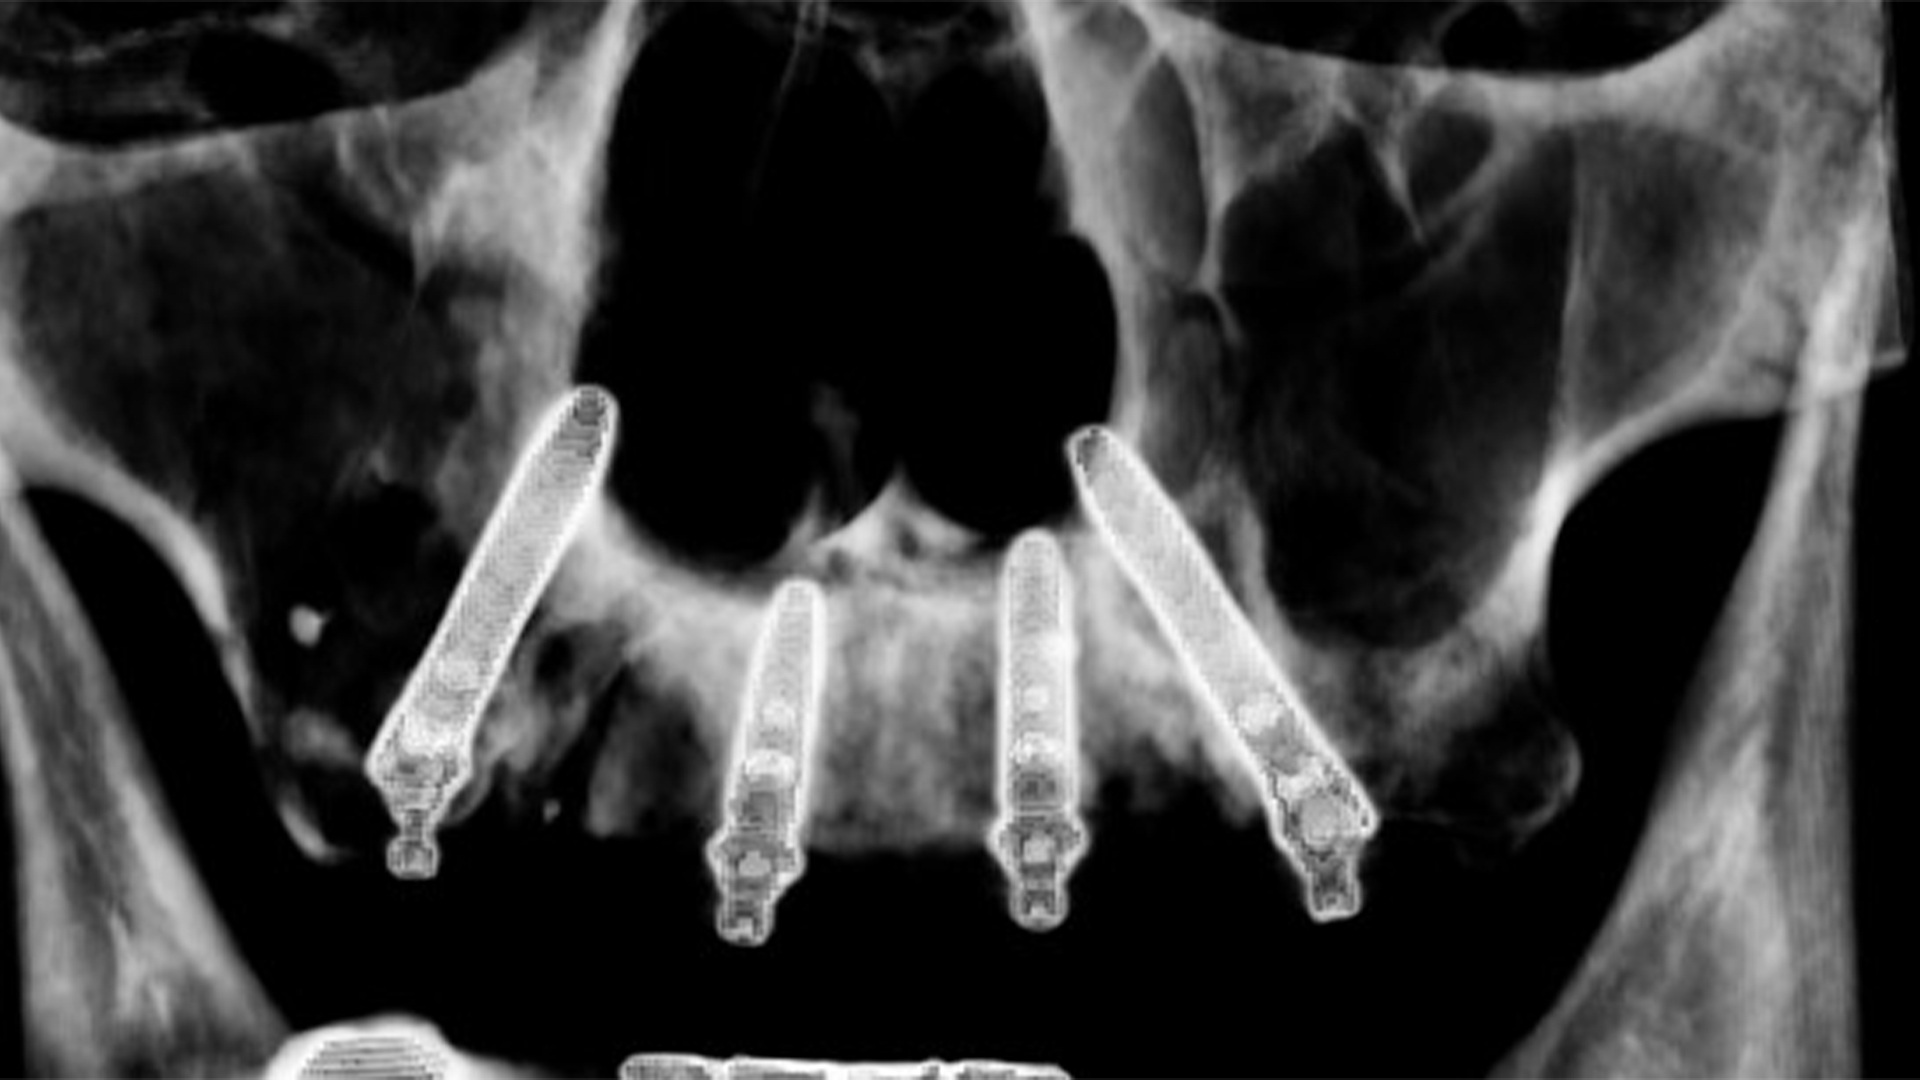

La tecnica di cui parliamo serve a risolvere casi di estrema atrofia prima di passare a tecniche ricostruttive o zigomatiche, è quindi molto difficile pensare di trovare casi che abbiano 5 millimetri di osso nella zona dei premolari… non sarebbero infatti casi atrofici ma casi banali alla portata di tutti.

“Quanti millimetri di osso crestale servono per un impianto transinusale?”….

Non c’è una regola. Anche zero se sei abbastanza esperto… beccati il video di questo caso!

Ma per ora vediamo come ho messo questi impianti.